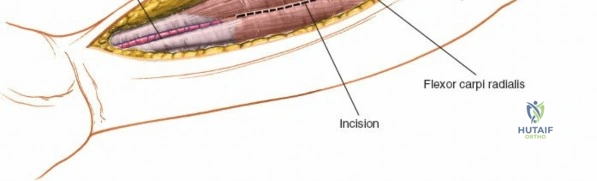

Accurate identification of surface landmarks is the first step in a successful Henry approach. Palpate the biceps tendon, a stout, taut structure crossing the anterior elbow joint just medial to the brachioradialis muscle. Next, palpate the brachioradialis itself, the fleshy muscle forming the lateral border of the cubital fossa. Finally, identify the styloid process of the radius distally. Note that when the forearm is fully supinated (the anatomic position), the radial styloid is truly lateral.

Make a straight or gently curved incision beginning at the anterior flexor crease of the elbow, just lateral to the biceps tendon. Extend this incision distally toward the styloid process of the radius. The exact length and placement of the incision are dictated by the specific pathology; the approach is highly modular, and often only the proximal, middle, or distal third of the incision is required.